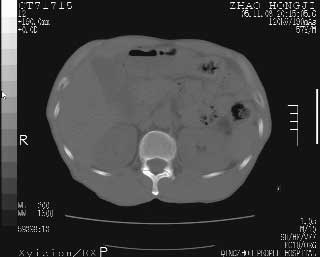

临床资料:男性,57岁,上腹部疼痛并5天,突然加重并延及全腹伴恶心5小时入院。胰淀粉酶化验在正常范围。检查:腹肌紧张,全腹压痛、反跳痛,尤以右上腹部为著。肠鸣音减低。血常规:wbc14.6x10/9, n:11.3x10/9 ,血压:135/90mmhg. 胸部透视:腹部肠腔轻度张气,未见其它异常改变。

肝右前缘少量积气,其他未见明显异常.考虑上消化道穿孔.

小网膜囊积气液,胃壁僵硬。考虑胃穿孔。

小膜网膜积液,肝缘气腹征,上消化道穿孔。

肝缘见少许气体,胰尾部见少许气体包饶(蓝色圈),12指肠上部或球部邻近胆囊周边也可见少许气体影(黄色圈),并忖托出胆囊壁,12指肠远段肠道内未见明显气体(白色箭)。

肝脏前缘见少量积气、胰尾部见少许气体包饶,肾前筋膜未见增厚,临床淀粉酶不高,意见:上消化道穿孔。

消化道穿孔。12指肠球部周和胰周积气考虑12指肠穿孔可能性大。

入院3小时后行剖腹探查术,见腹腔内大量脓性混浊液约1000ml,十二指肠球部溃疡穿孔,溃疡面约2.5x2cm,穿孔直径约0.6cm。胃内容物外益,周围组织炎性水肿明显。行十二指肠穿孔修补术。术后诊断:

1、十二指肠溃疡穿孔

2、弥漫性腹膜炎

对于少量的腹腔游离气体,ct检查较普通透视有绝对的优势,它不仅可以看到肝脏前上缘的气体,而且还能够看到小网膜区的游离气体。从而可以肯定诊断。各位分析战友的很好,感谢大家的参入!